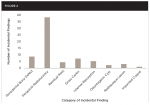

The incidental findings reported were divided into subcategories that included the presence of a periodontal bony defect, periapical radiolucency, residual root, gross caries, internal resorption, odontogenic cyst, radiopaque lesion, and impacted cuspid.The most frequent incidental findings were in the form of periapical radiolucencies (38 instances noted) (Figure 2). As can be seen in Figure 3, which shows the frequency of all incidental findings within each age group, 63 of the 69 incidental findings noted in this study were found in patients aged 41 years or older. Table 1 denotes both the category and number of incidental findings.